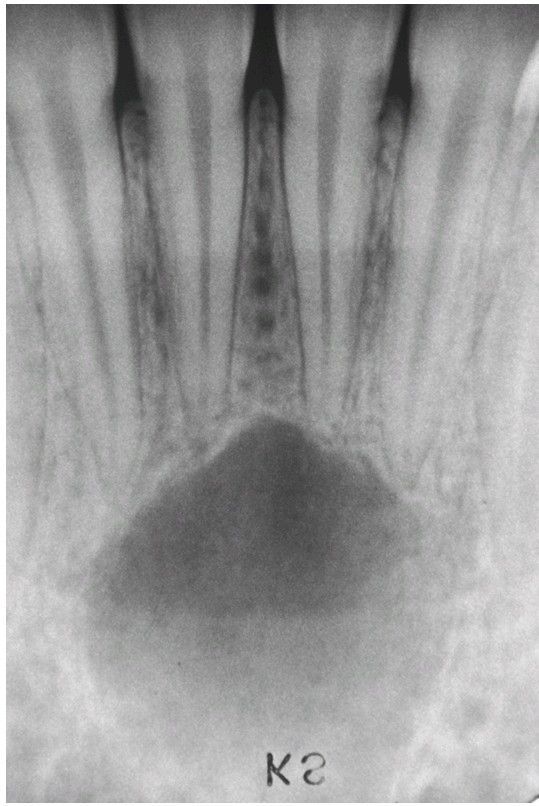

Simple Bone Cyst

Periapical radiograph showing a radiolucent area in the apical region of the anterior mandible. The incisor teeth responded normally to vitality testing, and no restorations are present.